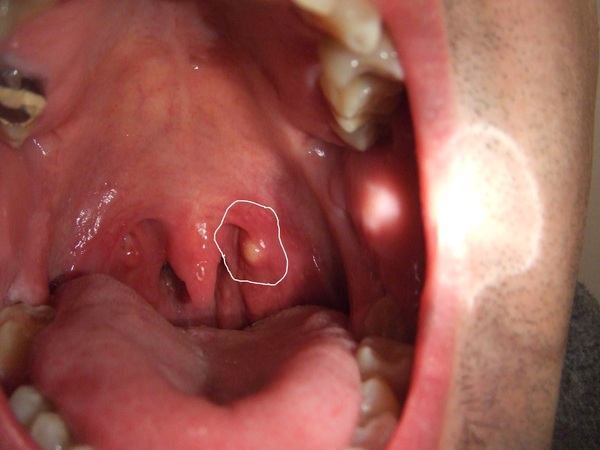

small white spot/ lump on the back of my mouth ton Images …

Bademcik Tümörü, Belirtileri ve Tedavisi – bademcik.gen.tr

white spots on back of throat, red spot in mouth cheek, red spots on throat, white spots in mouth, black spot in mouth, cyst in back of mouth, in back of mouth sore